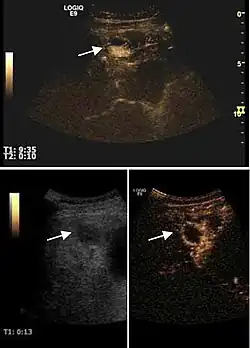

The ultrasound appearance is a well defined lesion, with very thin, almost unapparent walls, without circulatory signal at Doppler or CEUS investigation. The content is transonic suggesting fluid composition. The presence of membranes, abundant sediment or cysts inside is suggestive for parasitic, hydatid nature. Posterior from the lesion the acoustic enhancement phenomenon is seen, which strengthens the suspicion of fluid mass. They typically displace normal liver vessels but no vascular or biliary invasion occurs.

Hydatid liver cyst. Diagnostic criteria are the presence of membranes and sediment inside.